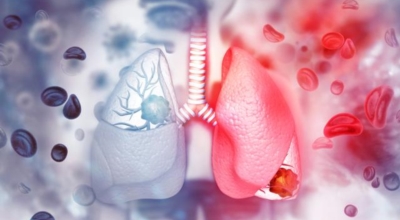

폐암 원인

폐암의 가장 큰 원인이며, 폐암 환자의 80-90%가 흡연에서 비롯될 수 있다고 할 수 있어요. 흡연을 자주 할 시 폐암 발생 위험이 흡연을 하지 않은 사람보다 13배가 증가를 할 수가 있고, 간접흡연 역시 1.5배나 폐암 걸릴 확률이 있어 흡연은 폐암 그 자체라고 생각하시면 될 것 같아요.

가족력으로 폐암에 걸릴 수가 있어요. 친척 포함 가족력 역시 폐암을 무시할 수가 없는데 가족 중 폐암을 가지고 있는 사람이 있을 경우 2~3배 발병률이 높는 것으로 알려져 있어요. 마지막은 생활환경이지요. 흡연 외에도 가스, 미세먼지, 암 유발 물질 노출, 대기오염 과 같은 생활환경에 따라 폐암이 발생할 수 있어요.